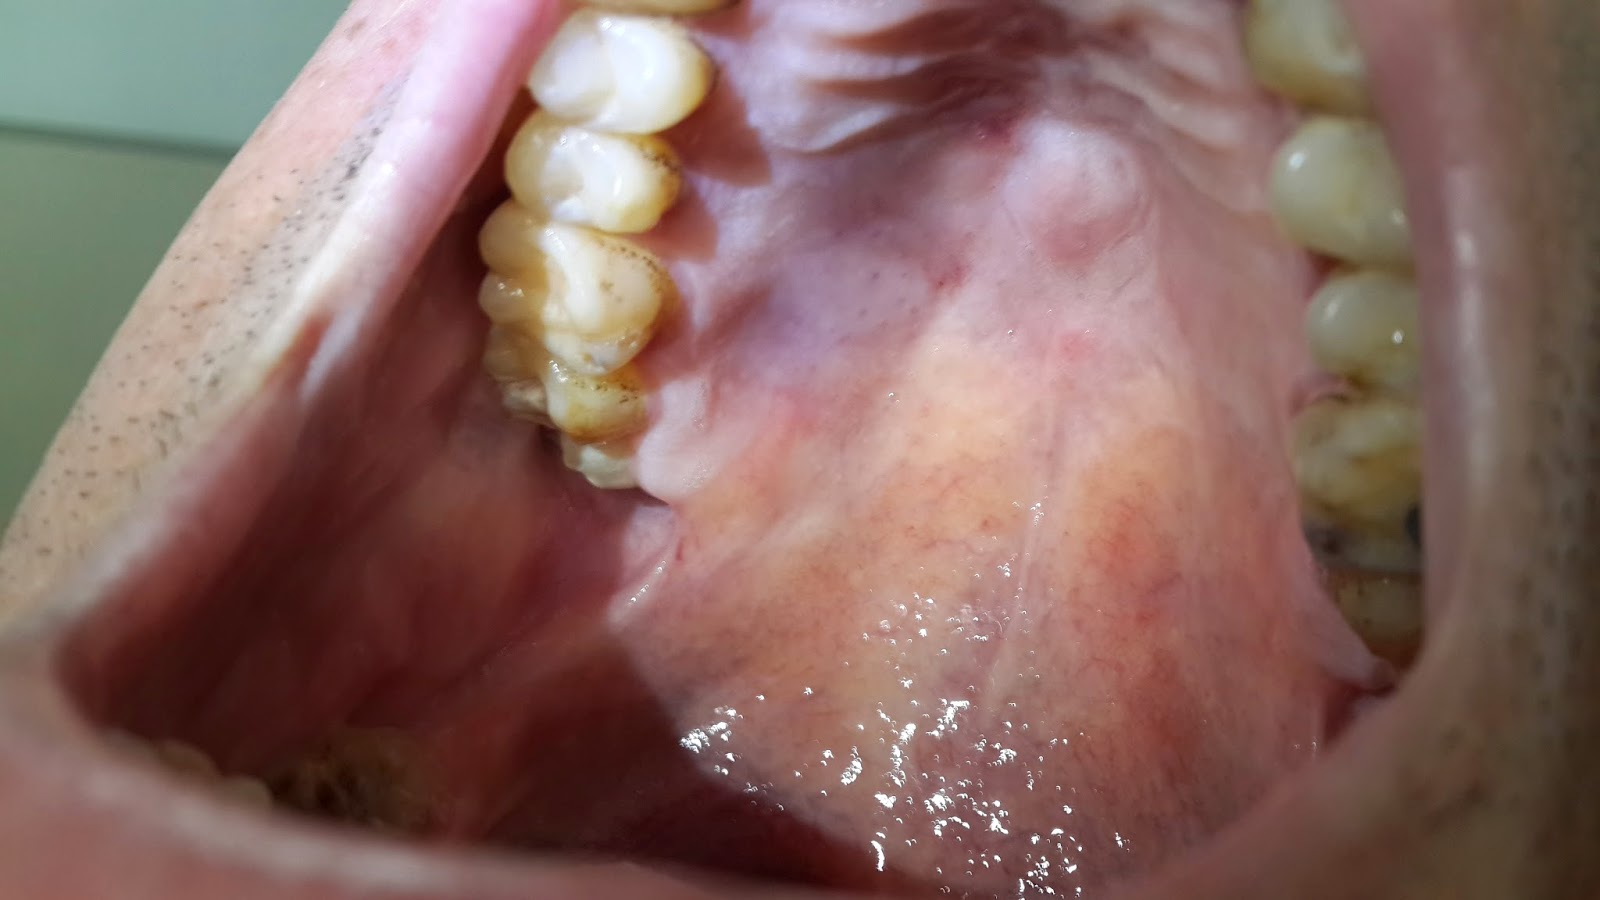

WebLa mayoría de las heridas leves, como pequeños cortes o raspones, pueden curarse por sí solas en unos pocos días. Sin embargo, las heridas más graves pueden tardar entre. WebEn un adulto los tiempos se prolongan considerablemente, pudiendo tardar hasta 3 años en colocarlo en su sitio, e incluso fracasar en el intento. Por supuesto, como ya te dicen, es. WebSegún expertos en odontología, cuando se extrae un diente, se genera tejido de granulación en pleno proceso de sanación de la inflamación. Éste, aparece dentro de una semana y protege la extracción hasta que se forme un hueso nuevo, lo cual puede tomar unas ocho semanas. En la cirugía de colgajo de las encías, un especialista ... WebEl tiempo de cicatrización es el período que tarda una herida en sanar. Y aunque el cuerpo humano ante una herida, comienza un proceso natural para controlar. WebPor lo general, el cirujano dental extraerá los puntos después de aproximadamente 1 semana. Algunas veces, la cirugía causa hematomas, hinchazón y dolor, que también requerirá tiempo para ... WebLa mayoría de las veces, la reparación del paladar hendido se hace cuando el niño es mayor, entre 9 meses y 1 año de edad. Esto permite que el paladar cambie a medida que el bebé crece. Realizar la reparación cuando el niño tiene esta edad ayudará a prevenir problemas posteriores en el lenguaje a medida que el niño se desarrolle. Web¿Cuánto tarda en cicatrizar una herida en el paladar? Sin embargo, en la farmacia es posible comprar medicamentos que te ayudarán a minimizar las molestias y acelerar el.

WebTiempos de cicatrización según área corporal perforada: - Cartílago de la oreja: de 6 a 7 meses. - Lóbulo de la oreja: de 4 a 6 semanas. - Ceja: de 6 a 8 semanas. - Fosas. Web¿Cuánto tiempo tarda en cicatrizar el paladar? Además de los puntos de sutura que al cabo de los días debe quitarte el dentista, también la escisión del paladar debe regenerarse.. WebSuele considerarse la etapa final de una enfermedad o lesión, y en algunos casos también supone el principio de un problema emocional en función de la localización, tamaño o forma de la cicatriz. La cicatrización es un proceso activo que se prolonga durante 12-18 meses. Podemos distinguir diferentes tipos: